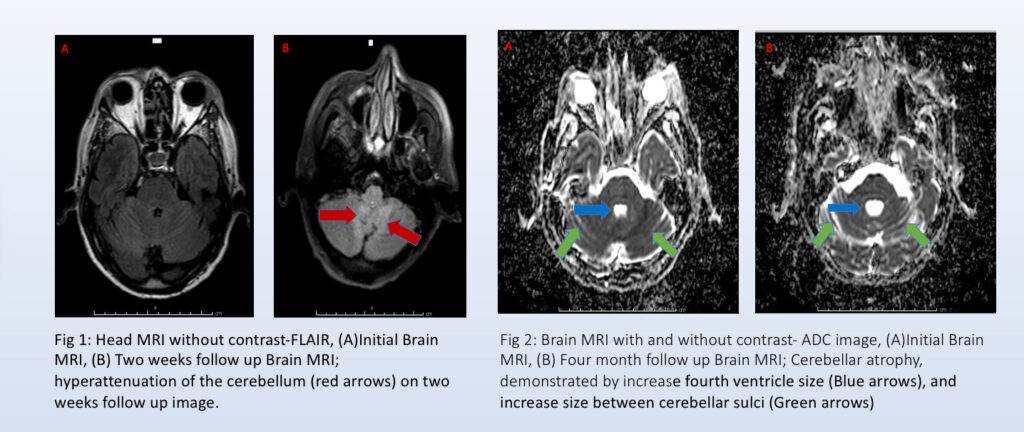

“Durante el transcurso de hospitalización fue referido al área de rehabilitación y dos meses más tarde se realizó nuevamente una resonancia magnética. Sin embargo, en esta ocasión, se empiezan a ver cambios en comparación con las resonancias magnéticas previamente realizadas, y vimos atrofia (en el área cerebral) y esto no es tan fácil de ver a simple vista, pero esto es uno de los primeros hallazgos que nos llevó a pensar que el paciente estaba sufriendo de cerebelitis”, abundó.

La cerebelitis se trata de un proceso inflamatorio del cerebro, pero más adelante este diagnóstico también fue descartado .

“Una de las causas más comunes de cerebelitis es cuando el paciente presenta infecciones, eventos isquémicos, precisamente los que que ya se habían descartado. Ya que el individuo tenía un historial de haber sido un fumador, vimos que una de las posibilidades era un síndrome paraneoplásico. Cuando se completa el análisis del líquido cefalorraquídeo, se demuestra precisamente que el paciente tenía este síndrome”, confirmó.